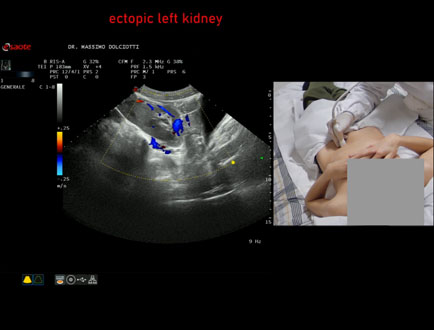

Motivazione dell'esame: riscontro occasionale di ectopia renale sinistra

Commento all'esame: le immagini ed il video documentano il rene sinistro ectopico in sede pelvica, di ecostruttura regolare e morfovolumetria normale, con diametro bipolare di 99 mm (v.n. 90-120 mm) x 37 mm, non dilatazione della via escretrice sinistra.

Conclusioni: rene sinistro ectopico (ectopic left kidney).